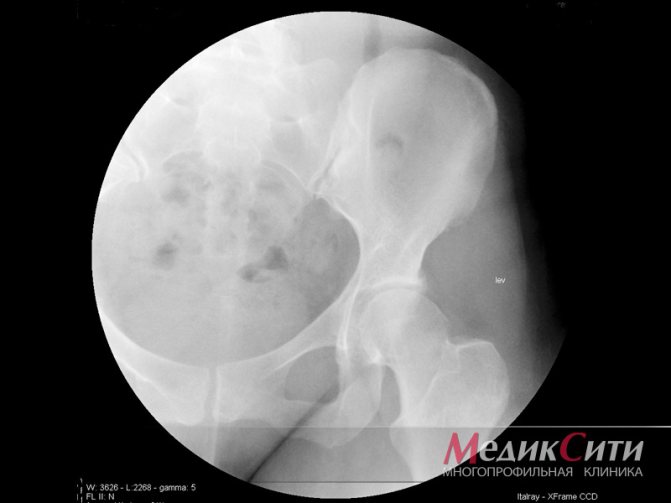

Главным методом определения болезни считается рентген. На начальных стадиях он не очень информативный, но в процессе развития может указать на существенные изменения в строении костно-хрящевой ткани. Рентгеновские признаки болезни — это тревожный сигнал. При незначительных нарушениях определяются изменения контуров суставов, расширение их просвета, а также разрушение костных краев. При активном развитии недуга отмечаются эрозийные образования на костной ткани. При этом на снимке видны деформационные изменения контуров костей и сокращение суставной щели. Рентген признаки появляются только через несколько месяцев после начала активного разрушения.

- Рентгенография позвоночника – позволяет обнаружить патологические изменения позвонков, характерные для спондилоартроза.

Рентгенологическое исследование. Часто является определяющим в постановке диагноза «спондилоартроз». На рентгенологическом снимке труднее распознать артроз суставов позвоночника, чем поражение более крупных суставов. Суставы позвоночника отличаются своим небольшим размером.

Однако рентгенологическая классификация стадий остеоартроза на них также распространяется:

- отсутствие рентгенологических признаков;

- сомнительные признаки;

- минимальные проявления в виде незначительного сужения суставных щелей и единичные остеофиты;

- умеренные проявления в виде прогрессирования сужения суставной щели и множественных остеофитов;

- выраженные проявления характеризуются практически полным отсутствием суставной щели и грубыми остеофитами.